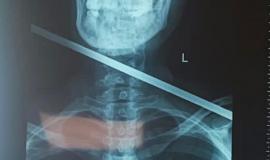

Приморские медики рассказали о спасении пациентки со стрелой в шее

Жительница поселка Трудовое чудом осталась жива после смертельного ранения